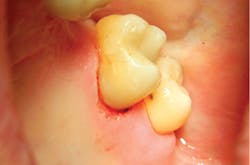

The removal of dental hard tissue is accomplished by what is known as thermomechanical photon-induced water-mediated ablation, which is a process in which the micro-explosive force of photons on water droplets results in the selective removal of carious dentin (figures 2a–2d). The laser energy seeks out tissue with higher water content, such as a carious lesion, and evaporates it without contact, vibration, or the introduction of microfractures, leaving the surrounding healthy enamel and dentin intact.

Figures 2a–2d: A Class II posterior cavity preparation